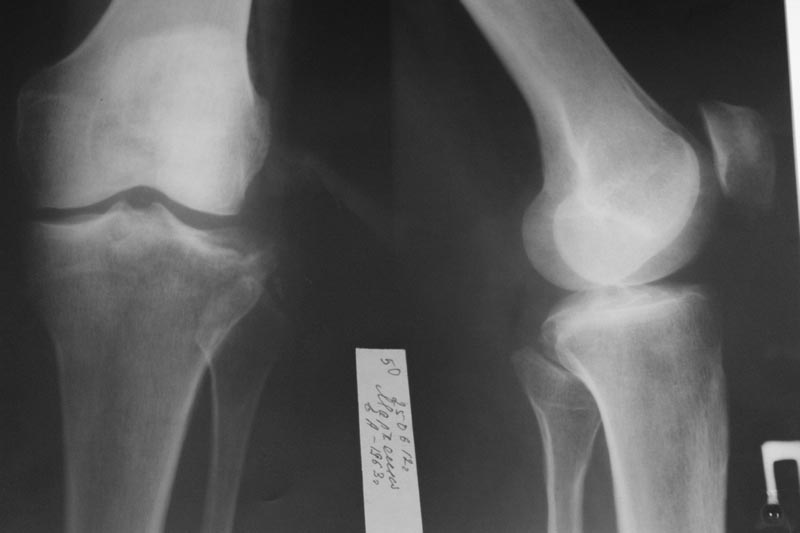

Пациентка М. 1963г.р. получила травму около 2 лет назад, лечилась в ЦРБ

по месту жительства консервативно. Обратилась в нашу клинику, на момент

осмотра имеется нестабильность сустава, боли в области сустава.

Предполагается э/протезирование мыщелка б/берцовой кости, либо

коррегирующая остеотомия. Помогите определиться с татикой лечения. Имеет

ли место альтернативные методы лечения?